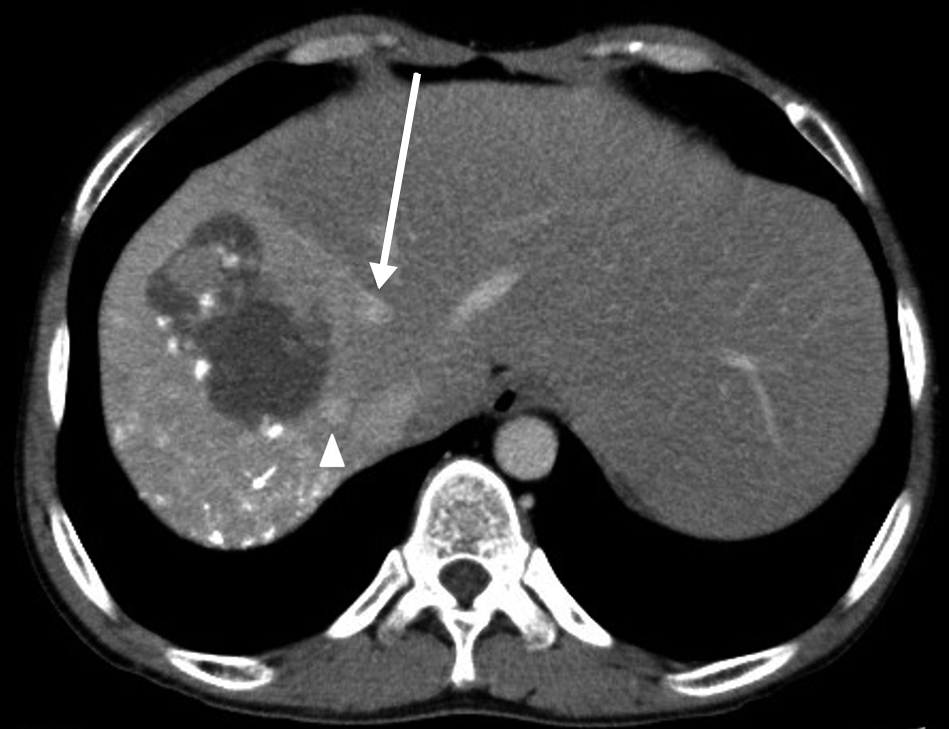

術後6日目未明に,突然の腹痛を訴えた.血圧108/64 mmHg,心拍数120回/分と,頻脈を呈し,血液検査でHb 4.4 g/dlと貧血を認めた.緊急腹部造影CTで,左右それぞれの下横隔動脈から,造影剤の血管外漏出像を認めたため(Fig. 4),血管造影検査を施行した.

Enhanced CT findings on postoperative day 6. a) Arterial phase shows extravasation of the contrast agent from the right inferior phrenic artery (arrowhead). b) Arterial phase shows extravasation of the contrast agent from the left inferior phrenic artery (arrow).